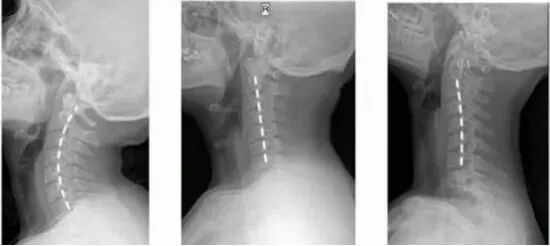

颈椎曲度变直

左图为颈椎正常的曲线,存在向前弯曲的弧线,右图为异常曲线,弧线凸向后方,称为颈椎反弓。

正常的颈椎是一个“C”型结构,颈椎有一个向前凸起,这是它的力学结构基础。这个“C”型的生理弧线保证了颈椎高度的灵活性和稳定性,这也是人体生理和功能的需要。 也正是由于这个生理弧度的存在,使得组成颈椎的7块小骨头能够承担整个头颅的重量,并完成各种动作。颈椎曲度是由于颈4至颈5椎间盘前厚后薄形成的,这也是人体生理结构的需要,同时不会让颈椎间盘突出。 但是,当由于各种原因颈椎曲度变直甚至颈椎反弓时,这个完美的弧形就不存在了。此时,颈椎不再拥有承受头颅重量的能力,不再能够缓冲压力,不再拥有颈4、颈5椎间盘前厚后薄的结构等,从而颈椎会发生退行性改变、颈间盘突出,造成疼痛、头晕、麻木等。 2. 颈椎曲度变直的原因 前凸的颈椎正像一张完美的弓形,而维持颈椎曲度的肌肉、韧带、椎间盘等软组织就像是拉紧的弓弦。这些结构的共同作用,维持了颈椎力学结构的稳定和神经管道的通畅。 当我们平视时,头颅的重心正好落在身体正中。而当我们长期伏案低头时,重心前移,力矩拉长,从而造成了软组织的疲劳,引起疼痛与不适。 久而久之,就如长期拉伸的皮筋一样,最终失去弹性,丧失了维持颈椎正常曲度的能力。从而进入了一个恶性循环,这就是我们常说的颈椎退变。 颈椎退变进一步的加重,则可导致椎间盘突出、骨赘形成、韧带肥厚等,从而对脊髓、神经、血管等重要结构造成挤压,造成肢体麻木、感觉活动功能异常等各类临床症状。 据研究,当我们平视前方时,我们颈椎所承受的负荷大约为5kg,而当我们以低头60°的姿势看手机时,颈椎所承受的负荷甚至可达到27kg。 27kg,这比我们举重比赛常用的最重的红色杠铃片还要再重2kg。按照以上的人均手机使用数据,合以目前我国的平均寿命计,约有985万分钟的时间在低头玩手机中度过。再算上工作、阅读等其他时间,相当于我们戴着一片杠铃一般的枷锁度过20~30年的有期徒刑。 根据颈椎病的不同临床表现,可以分为四大类: 1 颈型颈椎病 正常颈椎曲度 颈椎生理曲度变直 颈椎反弓 2 神经根型颈椎病 3 脊髓型颈椎病 4 其他型颈椎病